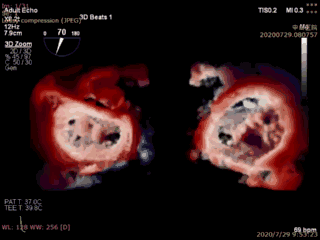

本例患者是一名70岁男性,术前超声心动图显示二尖瓣后叶冗长(前叶长度26mm,后叶长度20mm),瓣环前后径32mm,后叶p2关闭脱垂、连枷(脱垂宽度16mm,反流面积23.5cm2)。如此广泛的脱垂,使用国外同类产品完成经导管二尖瓣修复也是有极大挑战,经葛均波院士团队评估,多学科充分讨论后决定为该患者实施Valve Clamp二尖瓣夹合术。

首先在食道超声引导下,植入1枚IIIs型二尖瓣夹合器,释放后显示二尖瓣后叶仍有脱垂连枷,反流为轻中度,为改善患者远期疗效,遂再次植入1枚IIs型二尖瓣夹合器于A2P2的后瓣残余分流处,复查超声显示二尖瓣反流完全消失(0级),整个手术切口出血量几乎为零,手术取得圆满成功。